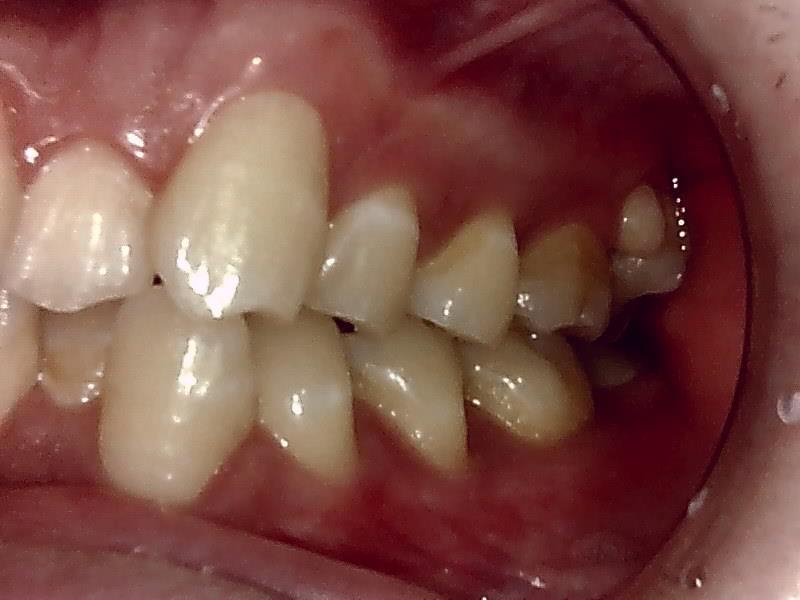

左側

右側

右側 術前の写真